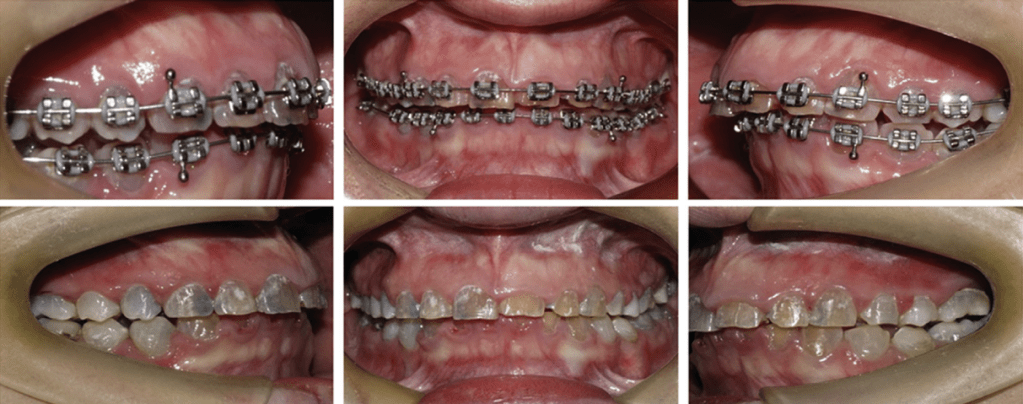

Ortodontia

A movimentação ortodôntica em pacientes com DI deve ser planejada com cautela, uma vez que a fragilidade dentária pode comprometer o resultado.

O acompanhamento integrado entre ortodontista e protesista é fundamental.